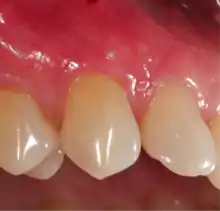

Exposure of the tooth root due to loss of keratinized tissue around the neck of a tooth is referred to as gingival recession. This can result in sensitivity or pain from the exposed tooth root surface (dentin is more permeable and soft compared to enamel and dentin is what makes up the tooth root).[7] Recession may also cause an unasthetic appearance especially if located in the anterior dentition (front teeth). While not all cases of gingival recession require surgical correction, there are various options if that is what the patient desires.[8] It should be reinforced that recession left untreated will not result in tooth loss, contrary to popular belief. Also, recession that is left untreated can be maintained and the inflammation kept at bay with proper brushing and oral hygiene technique.[5] On the other hand, if one desires to pursue corrective therapy, there are a wide variety of techniques ranging from autograft (your own tissue, usually taken from the palate), allograft (someone else's tissue, cadaver), xenograft (animal, usually porcine or bovine) or simply repositioning of the tissue native to the site.[9] The benefits of corrective therapy often result in decreased sensitivity through coverage of the root surface in addition to a gain in the keratinized tissue mentioned beforehand.

Gum grafting, also known as a gingival graft or periodontal plastic surgery, is a surgical procedure to reverse gum recession. Gum recession exposes the roots of teeth,[10] which can lead to sensitivity and put teeth at a higher risk of damage or disease[11] due to the loosening of their attachment within the gums and bones of the jaw. Should gum recession continue, bone and keratinized tissue will be at greater risk of being damaged and permanently lost around the teeth. The aim of a gum graft is to extend keratinized tissue of the gums to cover tooth roots,[12] which restores their firm placement within the jaw and prevents further damage.